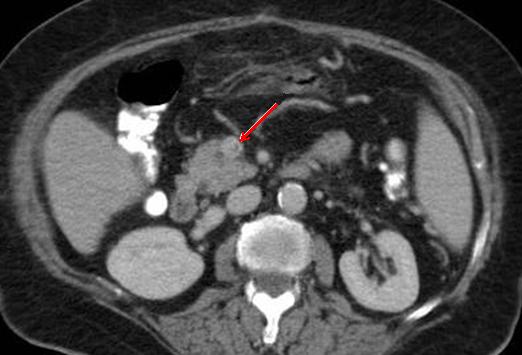

Aspect TDM une colite

ischemique avec image de gas intramurale du colon

sigmoide . Image radiologique TDM en coupe axiale a

travers sacrum S2 |

|

La presence de

gas au systeme portal intra hepatique dans colite

ischemique . Inmage radiologique TDM en coupe axiale |